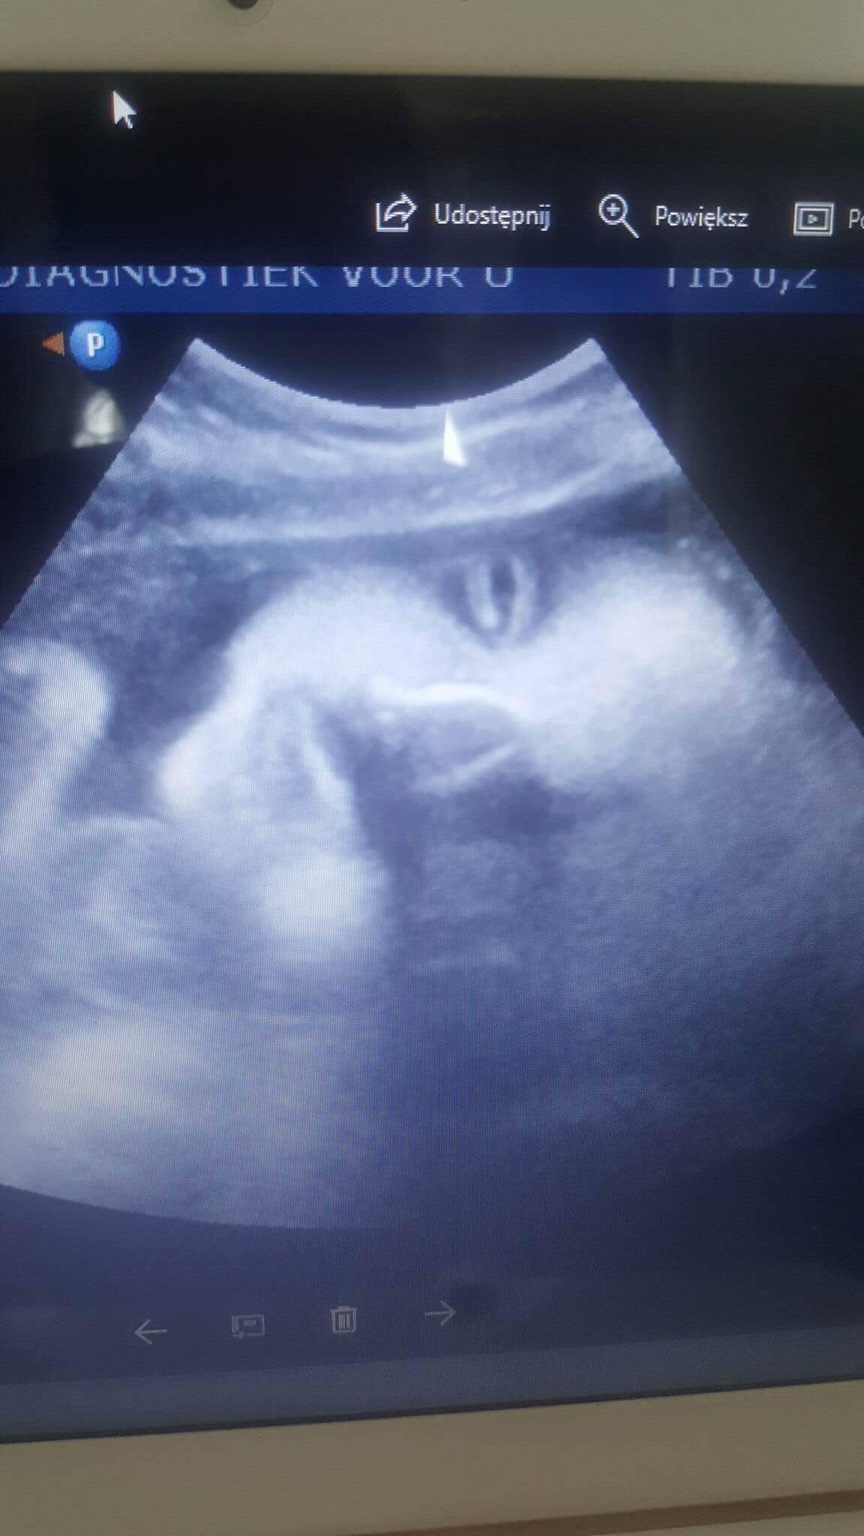

Co do usg i filmu, my w 12 tygodniu dostaliśmy film, zdjęcia i nagranie również w 3D/ 4D bez żadnych dopłat i próśb, po prostu tak dają, wiec teraz na połówkowych na pewno dostaniemy. To na prawdę fajna sprawa ;-) Ja polecam :-)